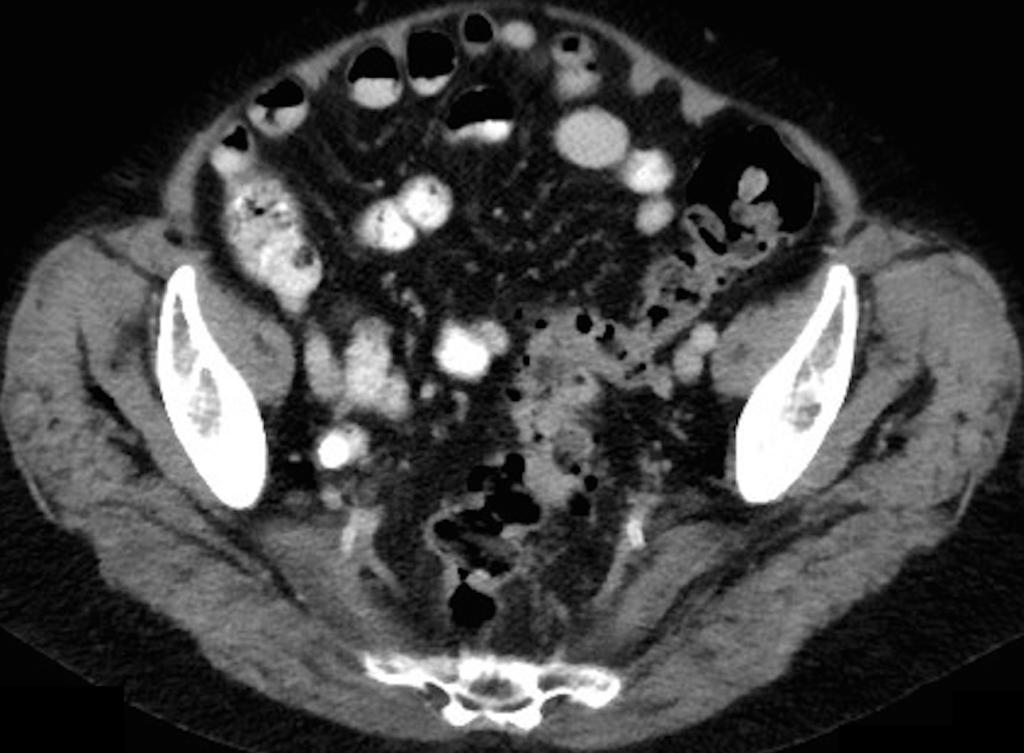

Een 78-jarige vrouw komt op de SEH wegens een pijnlijke rechter heup en koorts. Er is geen trauma voorafgegaan aan de klachten. Zij is bekend met polymyalgia rheumatica, waarvoor ze prednison gebruikt. De heup is drukpijnlijk, maar verder zijn er geen bijzonderheden en patiënte oogt niet ziek. De CRP-waarde is verhoogd. Op de CT-scan van het abdomen zijn duidelijke afwijkingen te zien.